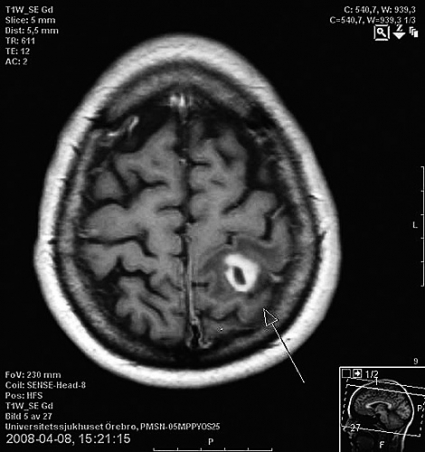

Fem år senare upptäcktes koloncancer, som patienten opererades för. Året därpå inkom hon akut på grund av domning i höger kroppshalva, oförmåga att tala och medvetandeförlust. Utredning med DT av hjärnan visade en centimeterstor, oregelbunden expansivitet parietalt (Figur 1), och i lungorna sågs multipla expansiviteter. Metastasering från kolontumören misstänktes. Efter upprepade undersökningar, inkluderande MR-undersökning, visade det sig finnas ännu en hjärnabscess. Vid eftergranskning av DT-undersökningen av lungorna såg man att förändringarna stämde väl överens med multipla arteriovenösa missbildningar av den sort som är associerad med hennes grundsjukdom, Mb Osler.

Hon behandlades även denna gång konservativt med antibiotika, och hjärnabscessen läkte ut utan neurologiska sequelae. De multipla pulmonella arteriovenösa missbildningarna bedömdes vara en avgörande faktor för uppkomsten av recidiverande hjärnabscesser, och diskussion fördes om huruvida de borde emboliseras. På grund av det stora antalet shuntar ansågs embolisering inte vara aktuell.

Tre år senare (i samband med att denna artikel skrevs) inkom patienten akut med epileptiska kramper sekundärt till en ny hjärnabscess. Denna gång skickades en remiss till Sveriges centrum för Mb Osler, lungkliniken vid Akademiska sjukhuset i Uppsala. Beslut togs nu om att embolisera de största arteriovenösa missbildningarna (Figur 2).